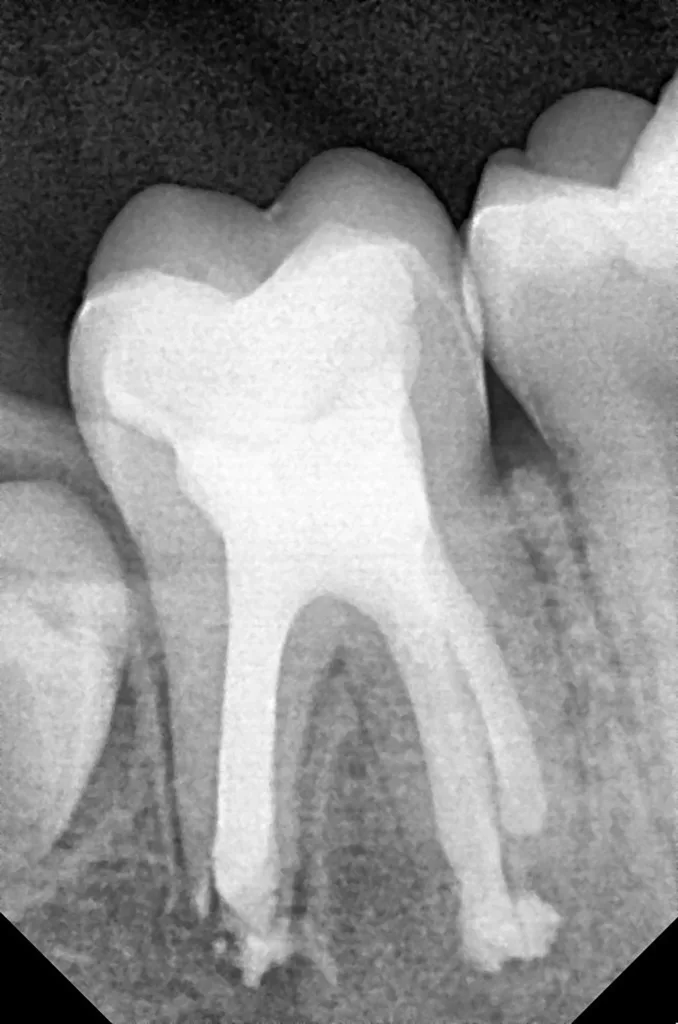

Im Rahmen der jährlichen Kontrolluntersuchung wurde bei einem achtjährigen Mädchen auf der routinemäßig angefertigten Röntgenaufnahme eine mittelgroße PEIR des Zahnes 46 (Grad 2 der Läsion nach Seow) entdeckt (Abb. 43). Die Patientin war komplett beschwerdefrei und der Zahnschmelz des betroffenen Zahnes sah intakt aus (Abb. 44 und 45). Weil auch hier der PEIR-Defekt gräulich durchschimmerte (Abb. 44 und 45) und der Zahn bereits seit einem Jahr durchgebrochen war, entschieden wir uns in diesem Fall, den Defekt klassisch mit Komposit zu restaurieren. Unter Lokalanästhesie mit Septanest 1/100 000 (Septodont, Frankreich) wurde zunächst Kofferdam mithilfe der Klammer U67 (KSK Dentech, Japan) gelegt (Abb. 45). Weder visuell noch mittels Sondierung konnte eine Verbindung zur Läsion festgestellt werden. Deswegen wurde an der Stelle, an welcher der PEIR-Defekt gräulich schimmerte, intakter Zahnschmelz der lingualen Querfissur entfernt (Abb. 46). Innerhalb der Läsion wurde nekrotisches intrakoronales Weichgewebe vorgefunden (Abb. 47), das problemlos mittels RONDOflex plus 360 (KaVo Dental, Deutschland) mit dem 27-µm-Pulver vollständig entfernt werden konnte. Der Boden des Defektes zeigte eine glatte, runde Form sowie helles, hartes und intaktes Dentin. Eine Präparation war nicht erforderlich, es wurde lediglich die Zahnschmelzkante geglättet (Abb. 48). Für die Restauration kamen erneut das Adhäsiv Optibond FL (Kerr, USA) und das Komposit Estelite ASTERIA OCE, A2B und Universal Flow AO2 (Tokuyama, Japan) zur Anwendung (Abb. 49). 6 Monate nach der Behandlung zeigte sich das Ergebnis sowohl aus klinischer als auch radiologischer Sicht stabil wie die Abbildungen 50 und 51 zeigen.